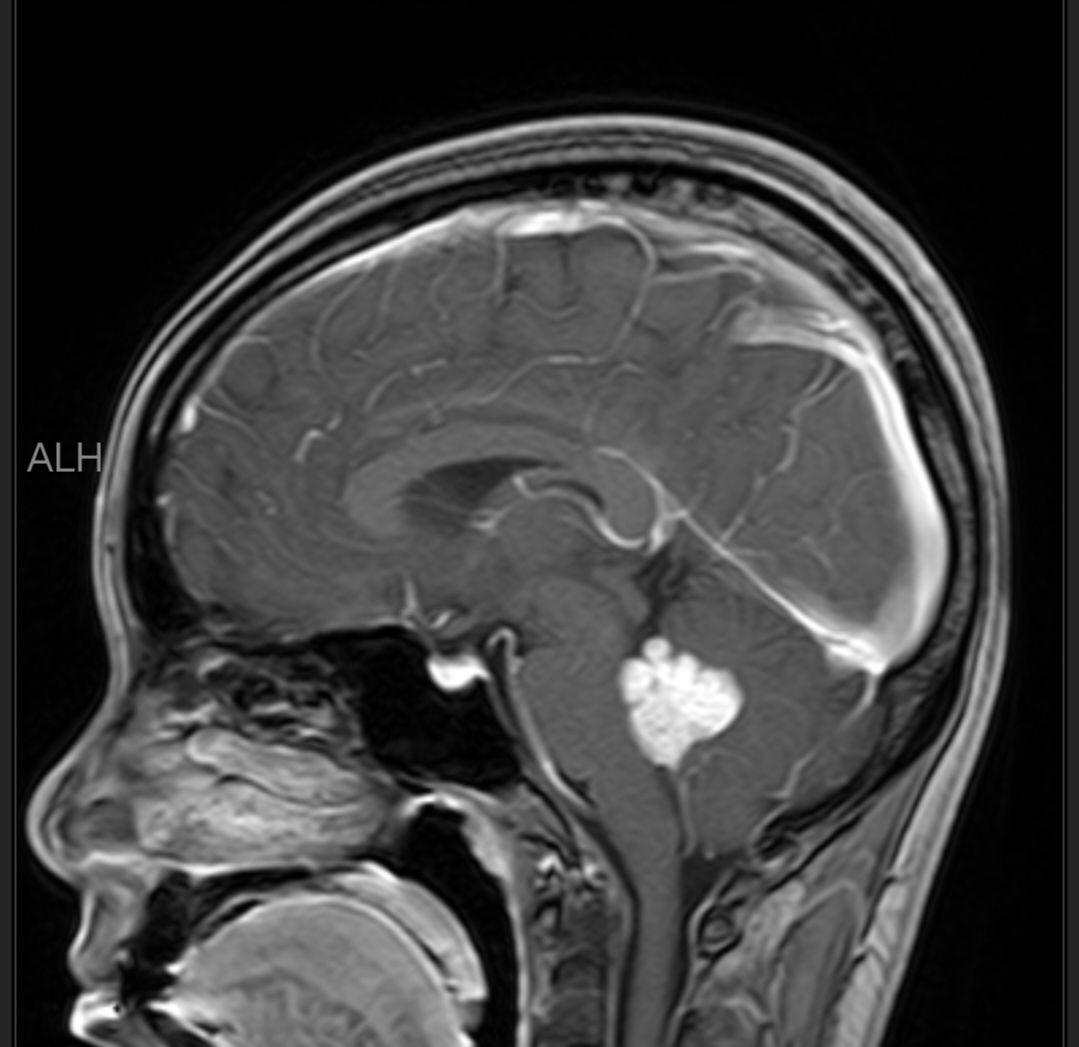

晒一下我的瘤子!希望它一个月后乖乖离开!